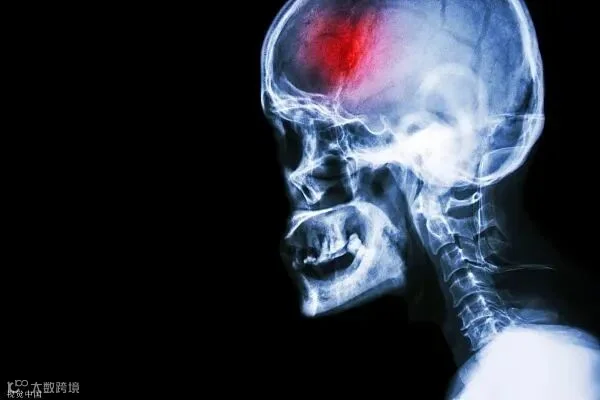

有人居然因一碗冰镇绿豆汤

加上自身基础疾病

诱发得了脑梗